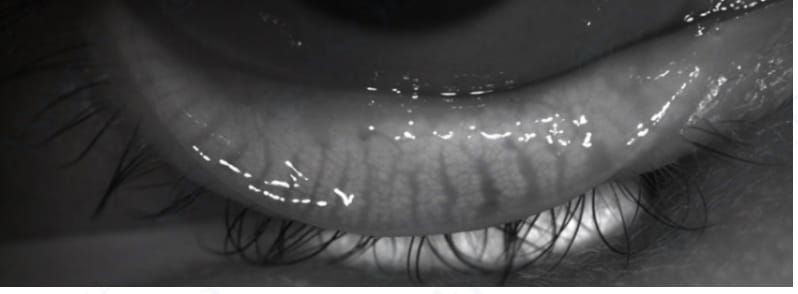

огляд за допомогою щілинної лампи: спостерігається дифузне виділення вмісту мейбомієвих залоз з канальців на інтрамаргінальних краях повіки, для повної візуалізації тканин повіку необхідно вивернути та оглянути зі сторони конʼюнктиви

1. Мейбомієва залоза - екзокринна (тобто така, що виділяє секрет на поверхню шкіри або слизової оболонки) сальна залоза, що продукує та виділяє ліпідний секрет, що складається з полярних та неполярних ліпідів, маслянистої консистенції, який є важливою складовою слізної плівки. Залози локалізуються в товщі верхньої (від 25 до 40 залоз) та нижньої (від 25 до 30 залоз) повік уздовж тарсальних пластинок і відкриваються своїми протоками на маргінальний край повіки.